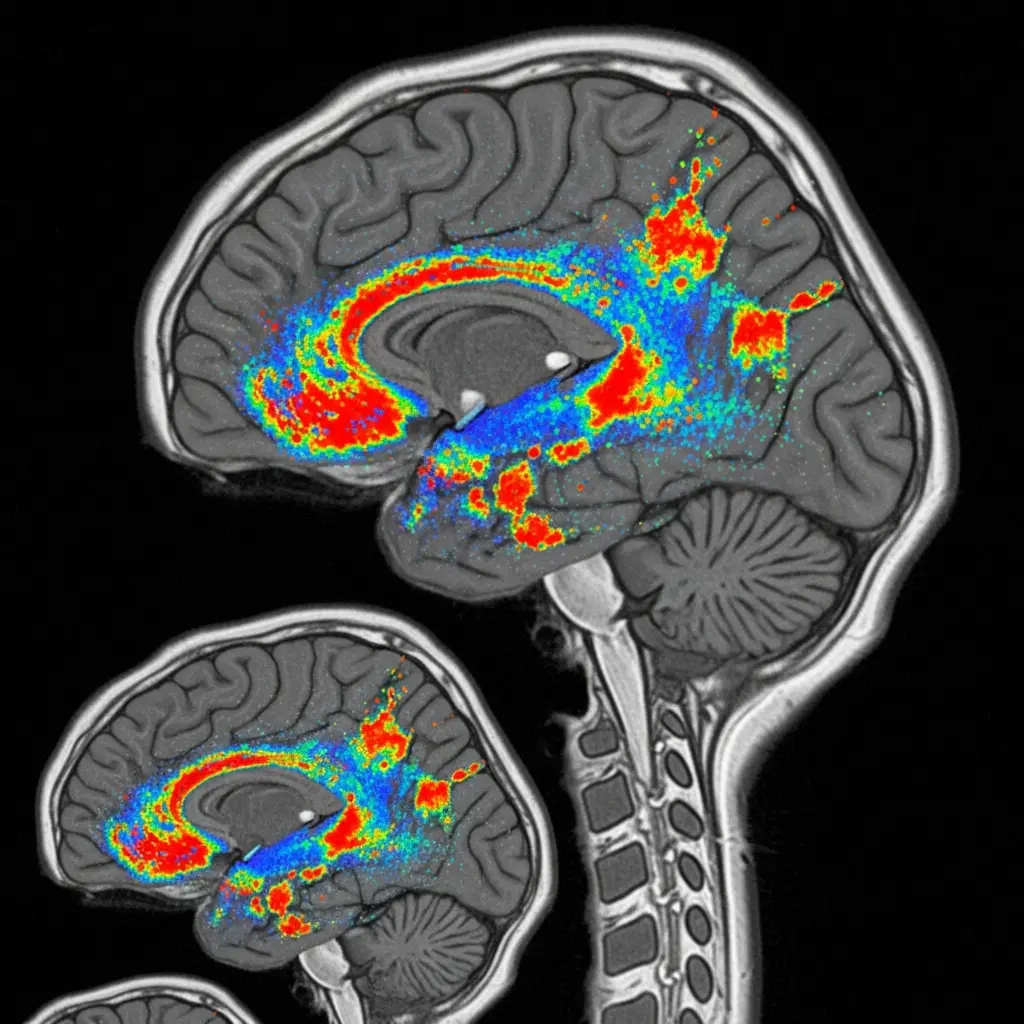

The study establishes a comprehensive benchmark suite encompassing 11 datasets and a diverse range of both resting-state and task-based fMRI tasks, facilitating reproducible and fair comparisons between models. Omni-fMRI’s dynamic patching mechanism intelligently assigns larger patches to less informative areas, while maintaining high resolution in functionally significant regions, optimising both memory usage and computational efficiency.

This efficiency allowed the use of a standard ViT architecture with global self-attention, effectively capturing long-range brain activities. Local spatiotemporal complexity was estimated using time-aggregated intensity variance, calculated as σ²P = 1/T Σt=1 EP[I²t] − (EP[It])², where It represents voxel intensity at time t and EP[·] is implemented via 3D average pooling.

This benchmark includes a diverse set of both resting-state and task-based fMRI tasks, ensuring robust evaluation. The dynamic patching mechanism assigns larger patches to background regions and maintains fine-grained resolution in functionally active areas, demonstrably reducing memory and computational demands.